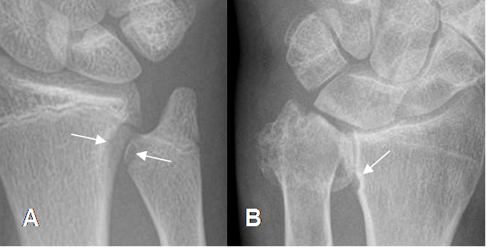

Fig 85. Pinzamiento ulnar.

A: Rx AP. Varianza ulnar negativa, con erosión en el tercio distal del radio y ulna.

B: Rx AP. Cambios degenerativos en el tercio distal de la ulna, que erosionan el radio distal.